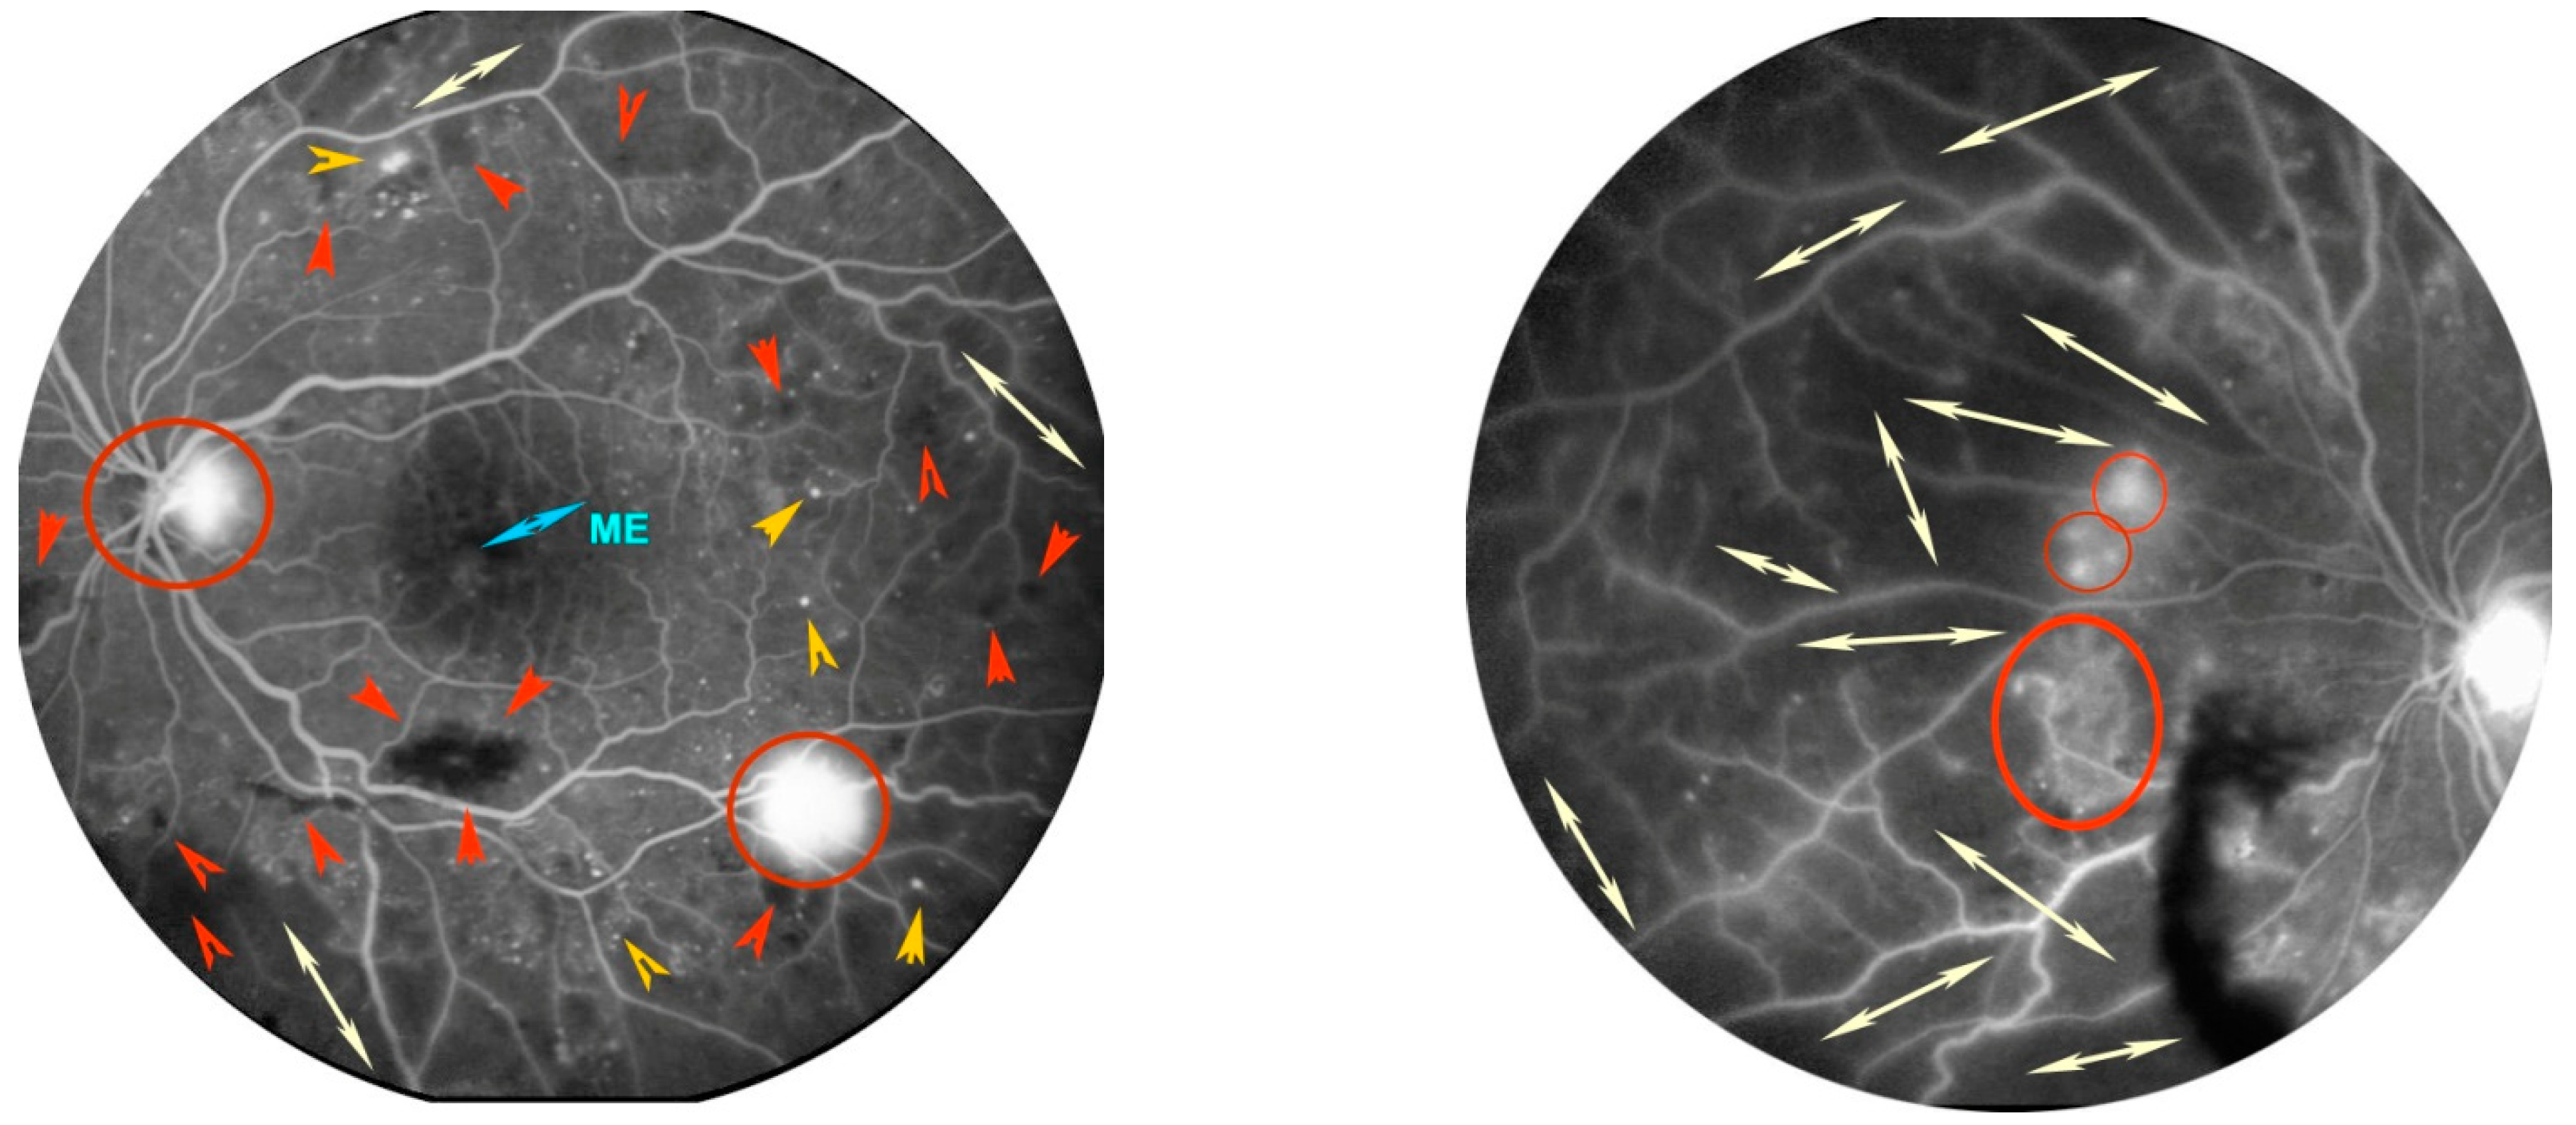

4.2. Diabetic Retinopathy (DR)